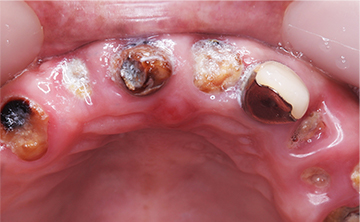

虫歯を放置して10年くらいの症例です。お口の中には、上あごは、一本しか歯が残っておらず、全く噛めないということで来院された患者さんです。痛い時期はどのようにして過ごされたのかと聞くと、とにかく痛み止めとお酒で痛みをごまかして過ごされたそうです。

すごい良く我慢されましたねとお伝えして、今後は、痛い時は安心してご来院くださいと伝えたら、ホッとされていました。小さい頃のトラウマで、とにかく歯科医院に行くことが怖かったそうです。

10年間虫歯を放置すると虫歯というより、歯が無くて噛めないので、咀嚼という問題が発生します。食べ物をお口の中へ入れても噛めないので、そのまま丸のみという食事になってしまうと胃や腸への負担は必須となり、癌や他の疾患へかかりやすますね。